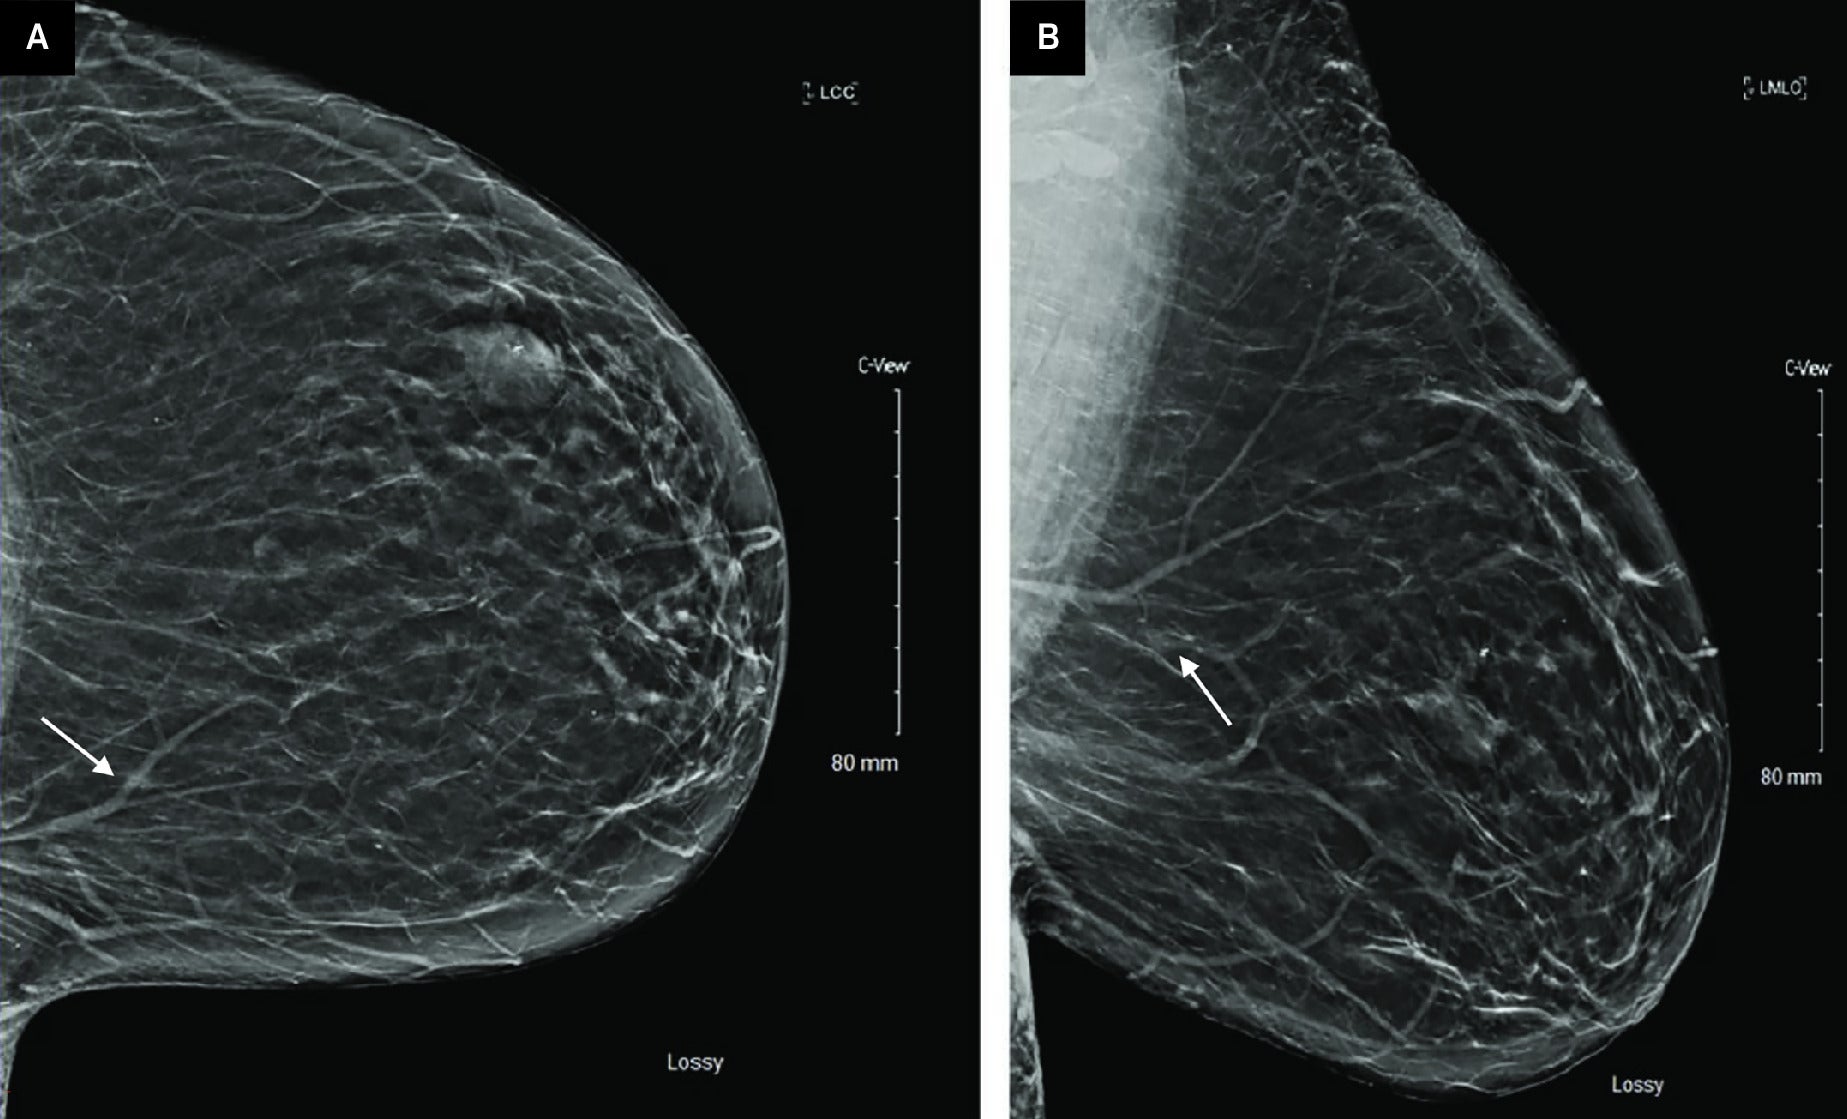

Screening full-field digital mammography with digital breast tomosynthesis (DBT) in craniocaudal (CC) and mediolateral oblique (MLO) projections demonstrated a 0.6-cm focal asymmetry in the upper inner left breast, posterior depth ( Figure 1 ). An additional previously biopsied fibroadenoma in the left breast with biopsy marker was stable.

Screening full-field digital mammography with DBT of the left breast in the CC (A) and MLO (B) projections demonstrates a focal asymmetry in the left breast upper inner quadrant, posterior depth (arrows). An additional stable fibroadenoma in the upper outer left breast, middle depth (arrowhead)